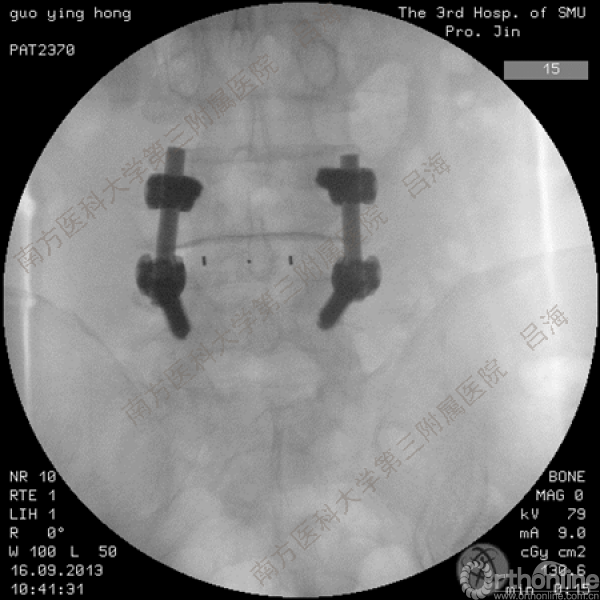

随着社会老龄化进程加快,胸腰椎退行性病变的治疗已经成为脊柱学术界的一个热点话题。MIS-TLIF手术可以治疗多种不同的胸腰椎退行性疾病,南方医科大学第三附属医院吕海教授结合病例为我们一一展示了该术式在治疗不同胸腰椎疾病时的具体手术过程。